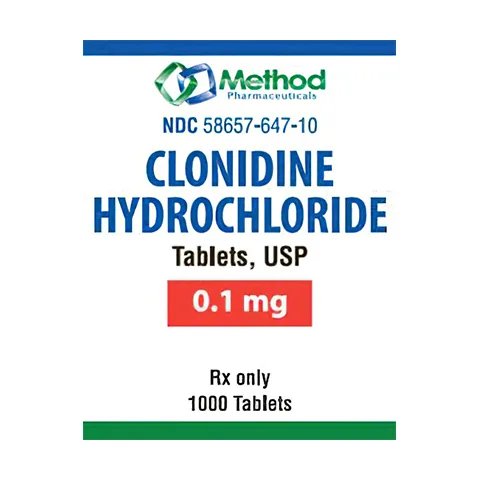

Featured products

Ready to deliver better care?

Explore our extensive range of cost-effective alternatives to popular medications tailored for your pharmacy.